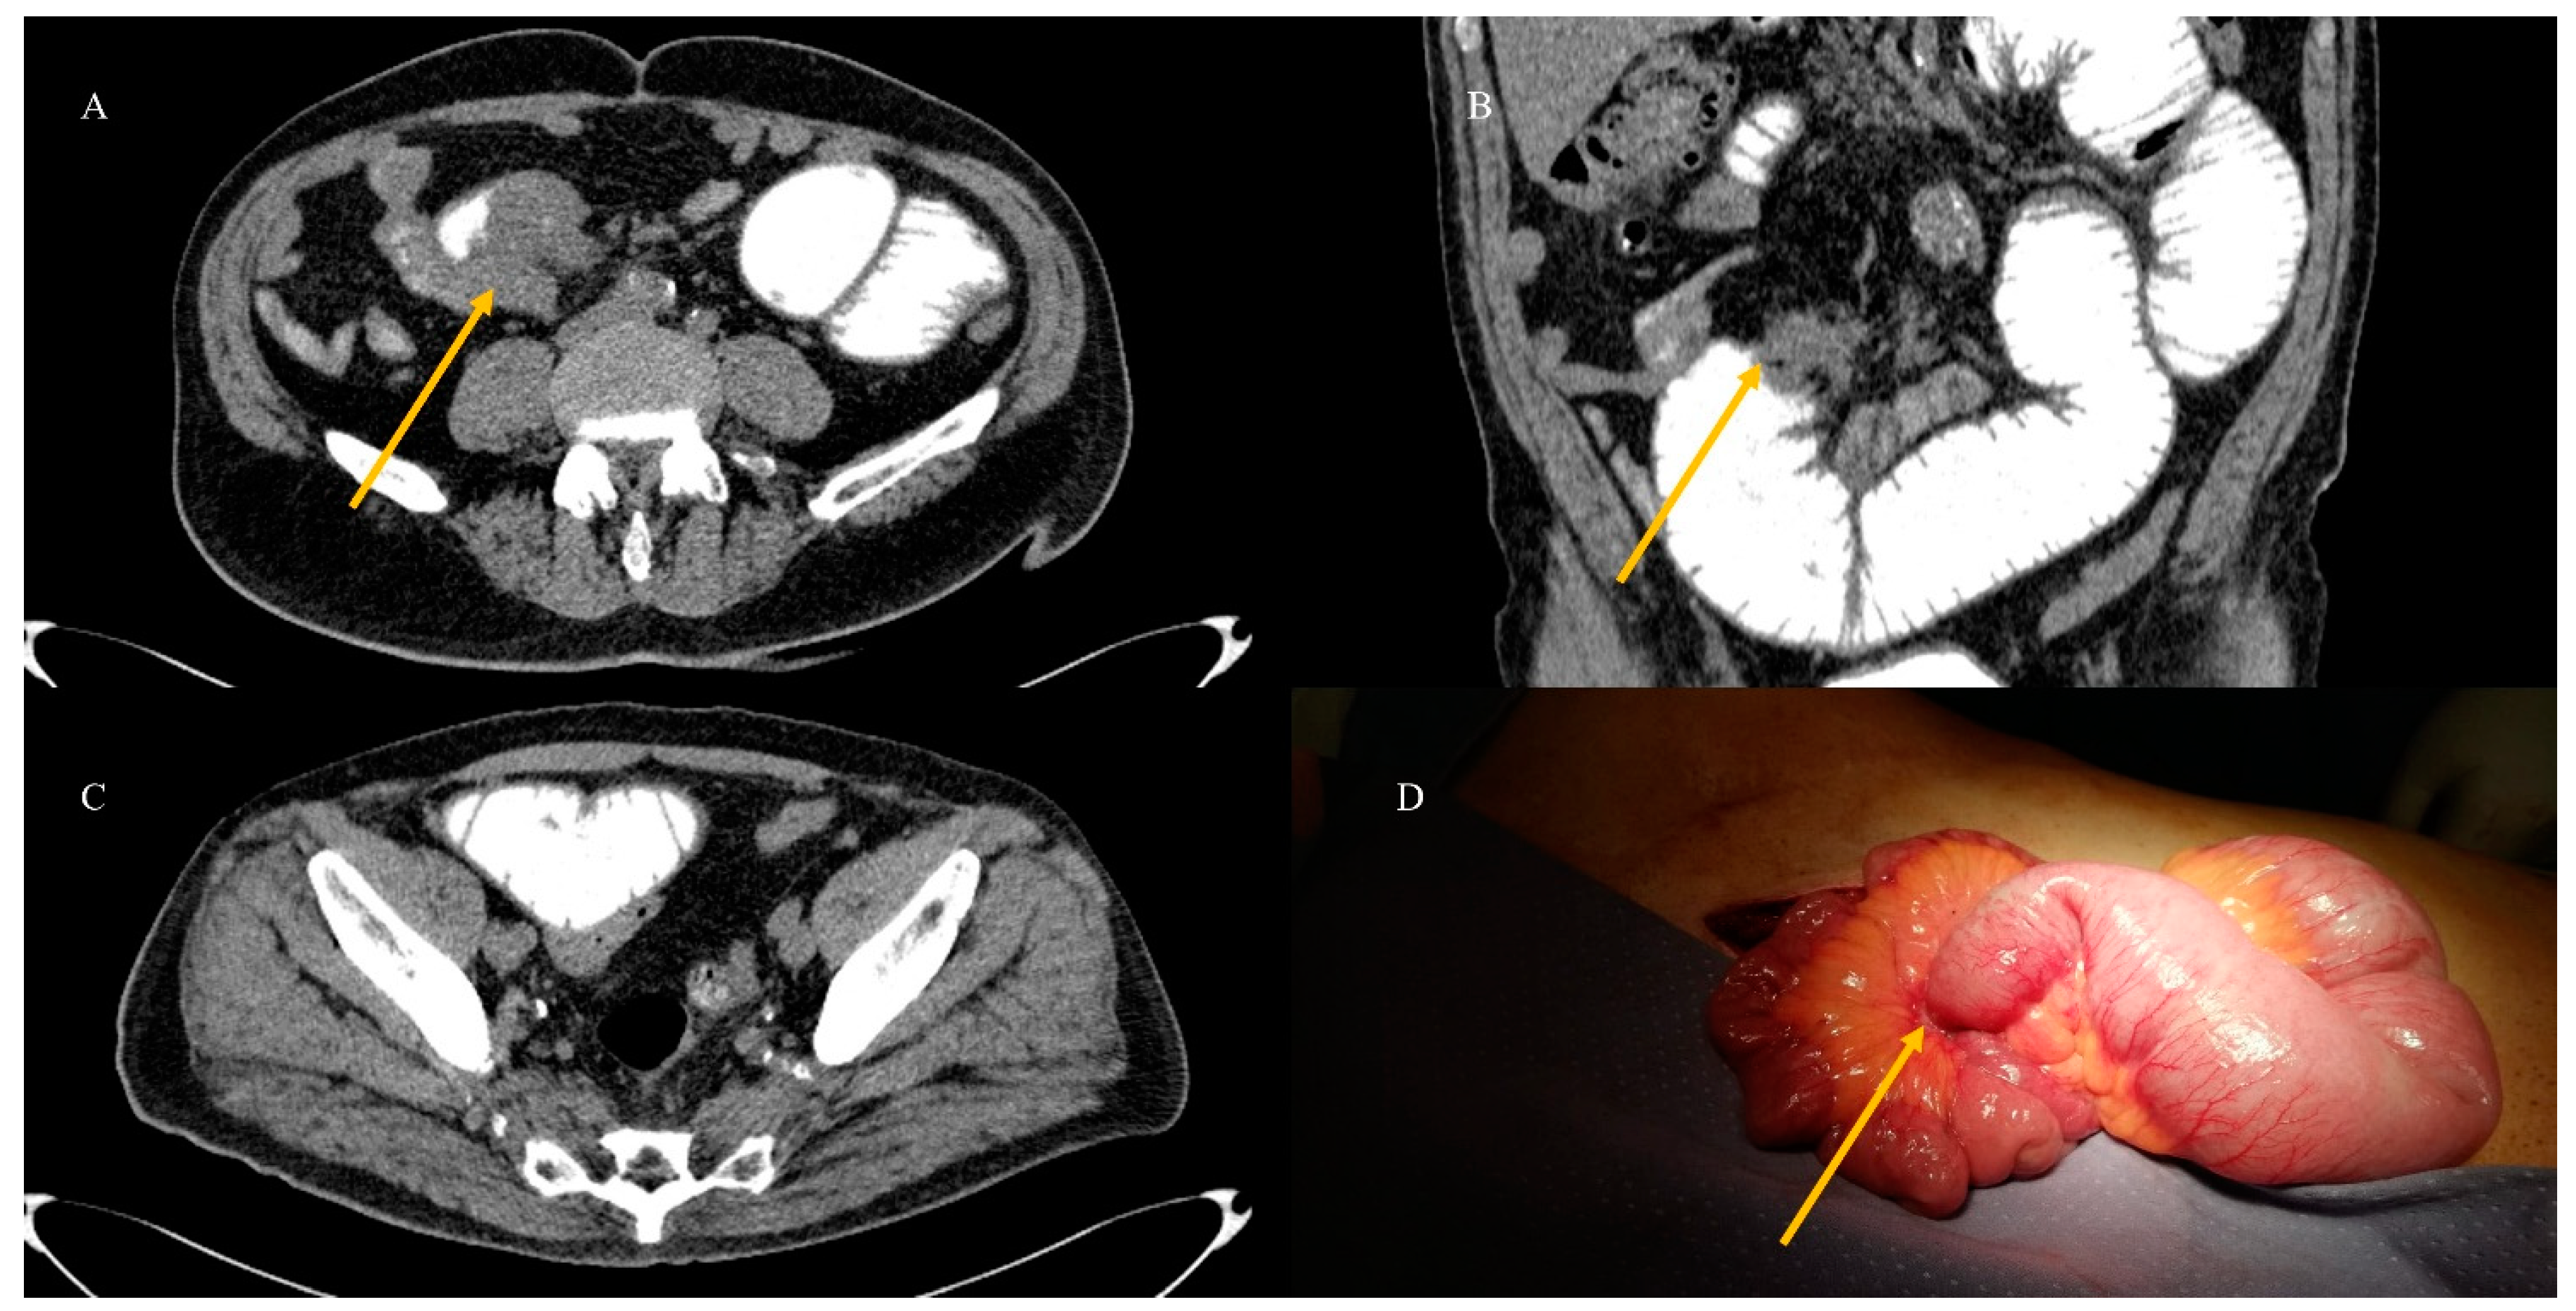

2.3. Small Bowel Tumor Presentation in Emergencies with Intestinal Intussusception

- Brogna, B.; Imbriani, G.C.; Forte, N.R.; Schettino, M.; Morelli, R.; Venditti, M.; Manganiello, C.; Biondo, F.G. Multifocal gastrointestinal stromal tumor: A case report with CT, surgical, and histopathologic correlation. Radiol. Case Rep. 2019, 14, 962–966. [Google Scholar] [CrossRef] [PubMed]

- Marsicovetere, P.; Ivatury, S.J.; White, B.; Holubar, S.D. Intestinal intussusception: Etiology, diagnosis, and treatment. Clin. Colon. Rectal Surg. 2017, 30, 30–39. [Google Scholar] [CrossRef] [PubMed]

- Kim, Y.H.; Blake, M.A.; Harisinghani, M.G.; Archer-Arroyo, K.; Hahn, P.F.; Pitman, M.B.; Mueller, P.R. Adult intestinal intussusception: CT appearances and identification of a causative lead point. Radiographics 2006, 26, 733–744. [Google Scholar] [CrossRef]

- Panzera, F.; Di Venere, B.; Rizzi, M.; Biscaglia, A.; Praticò, C.A.; Nasti, G.; Mardighian, A.; Nunes, T.F.; Inchingolo, R. Bowel intussusception in adult: Prevalence, diagnostic tools and therapy. World J. Methodol. 2021, 11, 81. [Google Scholar] [CrossRef] [PubMed]